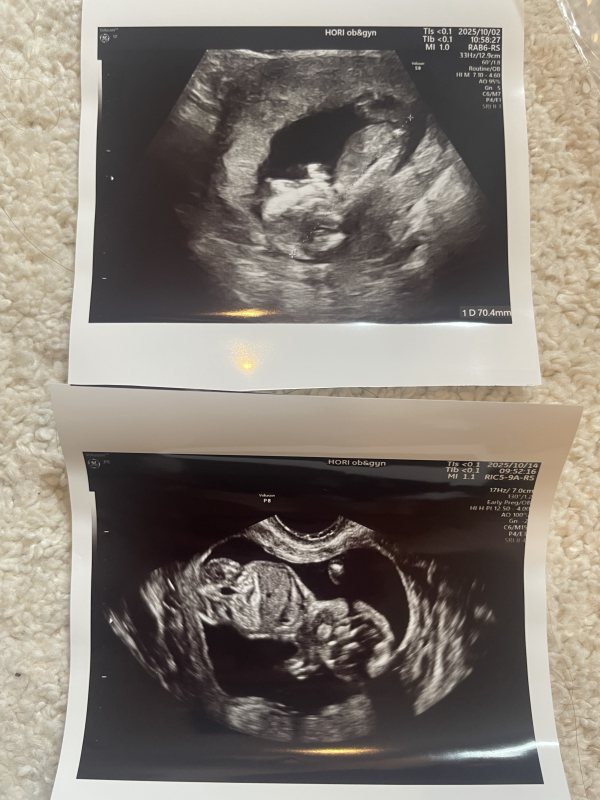

胎児の大きさが13w0dの健診では70mmでした。

※上の画像が13wのものです。